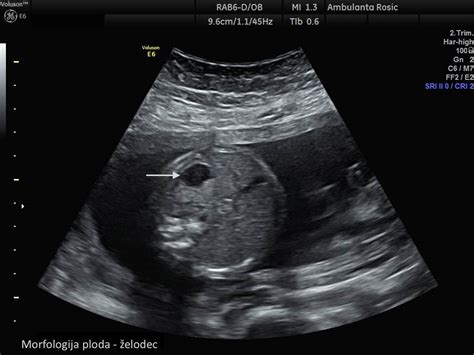

Ocenjevanje količine plodovnice

Količino plodovnice ocenjujemo z več metodami. Ultrazvočne preiskave so ključne za vizualizacijo in kvantifikacijo plodovnice. Posebna ultrazvočna metoda, imenovana indeks plodovnice (AFI - Amniotic Fluid Index), omogoča natančnejše merjenje, pri čemer se maternica razdeli na štiri kvadrante in se izmeri globina najglobljega amniotskega žepa v vsakem od njih. Seštevek teh meritev nam da skupni AFI. Poleg ultrazvoka lahko zdravniki uporabijo tudi ginekološki pregled in posebne teste, ki pomagajo pri oceni stanja.